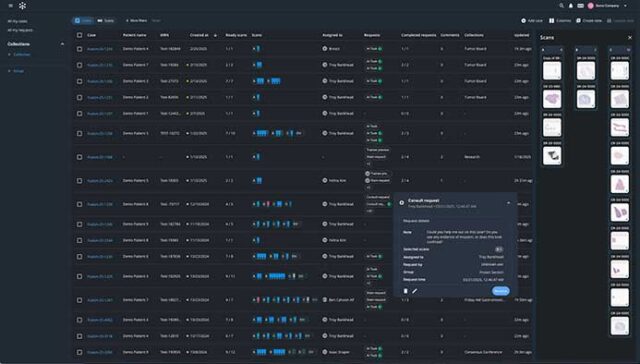

Built with pathologists to deliver an ultrafast cloud-based viewer, flexible worklist, integrated workflows, and state-of-the-art AI.

Techcyte Fusion: The unified anatomic and clinical pathology AI platform

What to expect from the Techcyte platform